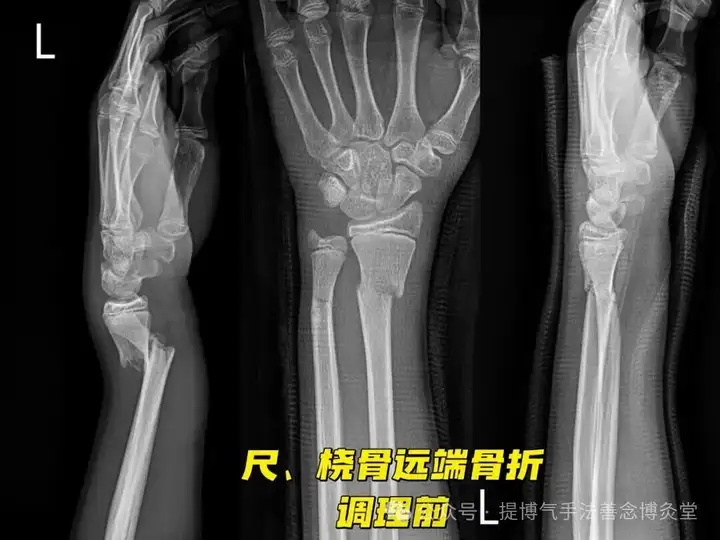

时间2024年10月17号,患者男,15岁,宁波人士,摔跤导致手臂尺、桡骨远端错位骨折。

调理方案:

- 回医瞬间接骨术

- 按跷升血疗法

- 元阳灸补气散寒

- 破砂散服用

- 服用枸杞原浆补血

调理时间:2个疗程。持续休养2个月

调理师:陈伟、吕丽

调理效果:骨折痊愈,患者因严重缺血而恢复缓慢!